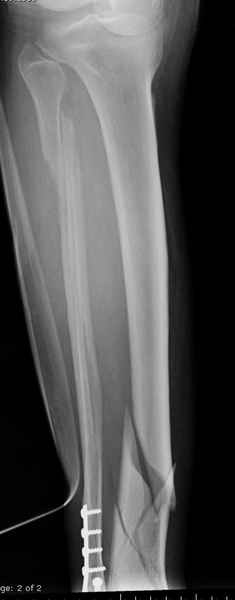

Здесь мы использовали новый Synthes Nail с дополнительными дырками, в проксимальной части 4: по две косых и поперечные (один стандартный а другой динамический), в дистальной части две поперечные, прямая и косая. Вес больного более 120 кг, нагрузку начнем через месяц.

Получилось красиво, поздравляю. Вверху можно было ограничиться одним винтом во фронтальное статическое отверстие, зачем два 45-градусных?

При такий спирали задний край tibia может быть сломан - нет ли этого в данном случае? На всякий случай можно было ввести 1-2 винта 4,5 мм спереди назад мимо гвоздя. Хотя самый дистальный блокирующий винт, возможно, зацепил этот отломок. А какой тут диаметр гвоздя и locking винтов?

DK> косая. Вес больного более 120 кг, нагрузку начнем через месяц.

Если там и правда сломан задний край, то лучше с нагрузкой подождать, даже будь больной полегче.